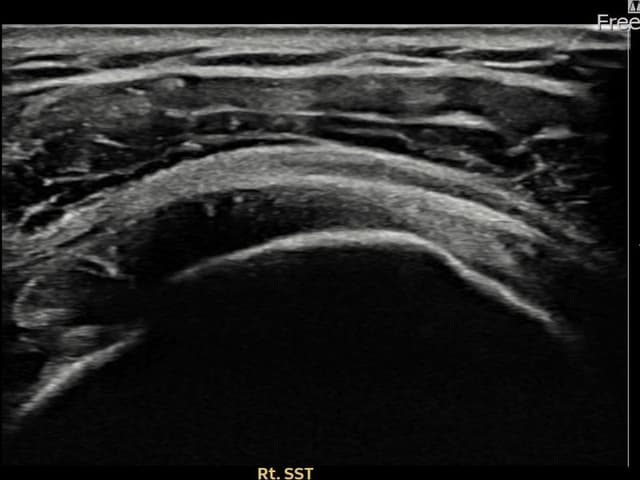

右侧 冈上肌腱 石灰化肌腱炎

14mm × 10mm